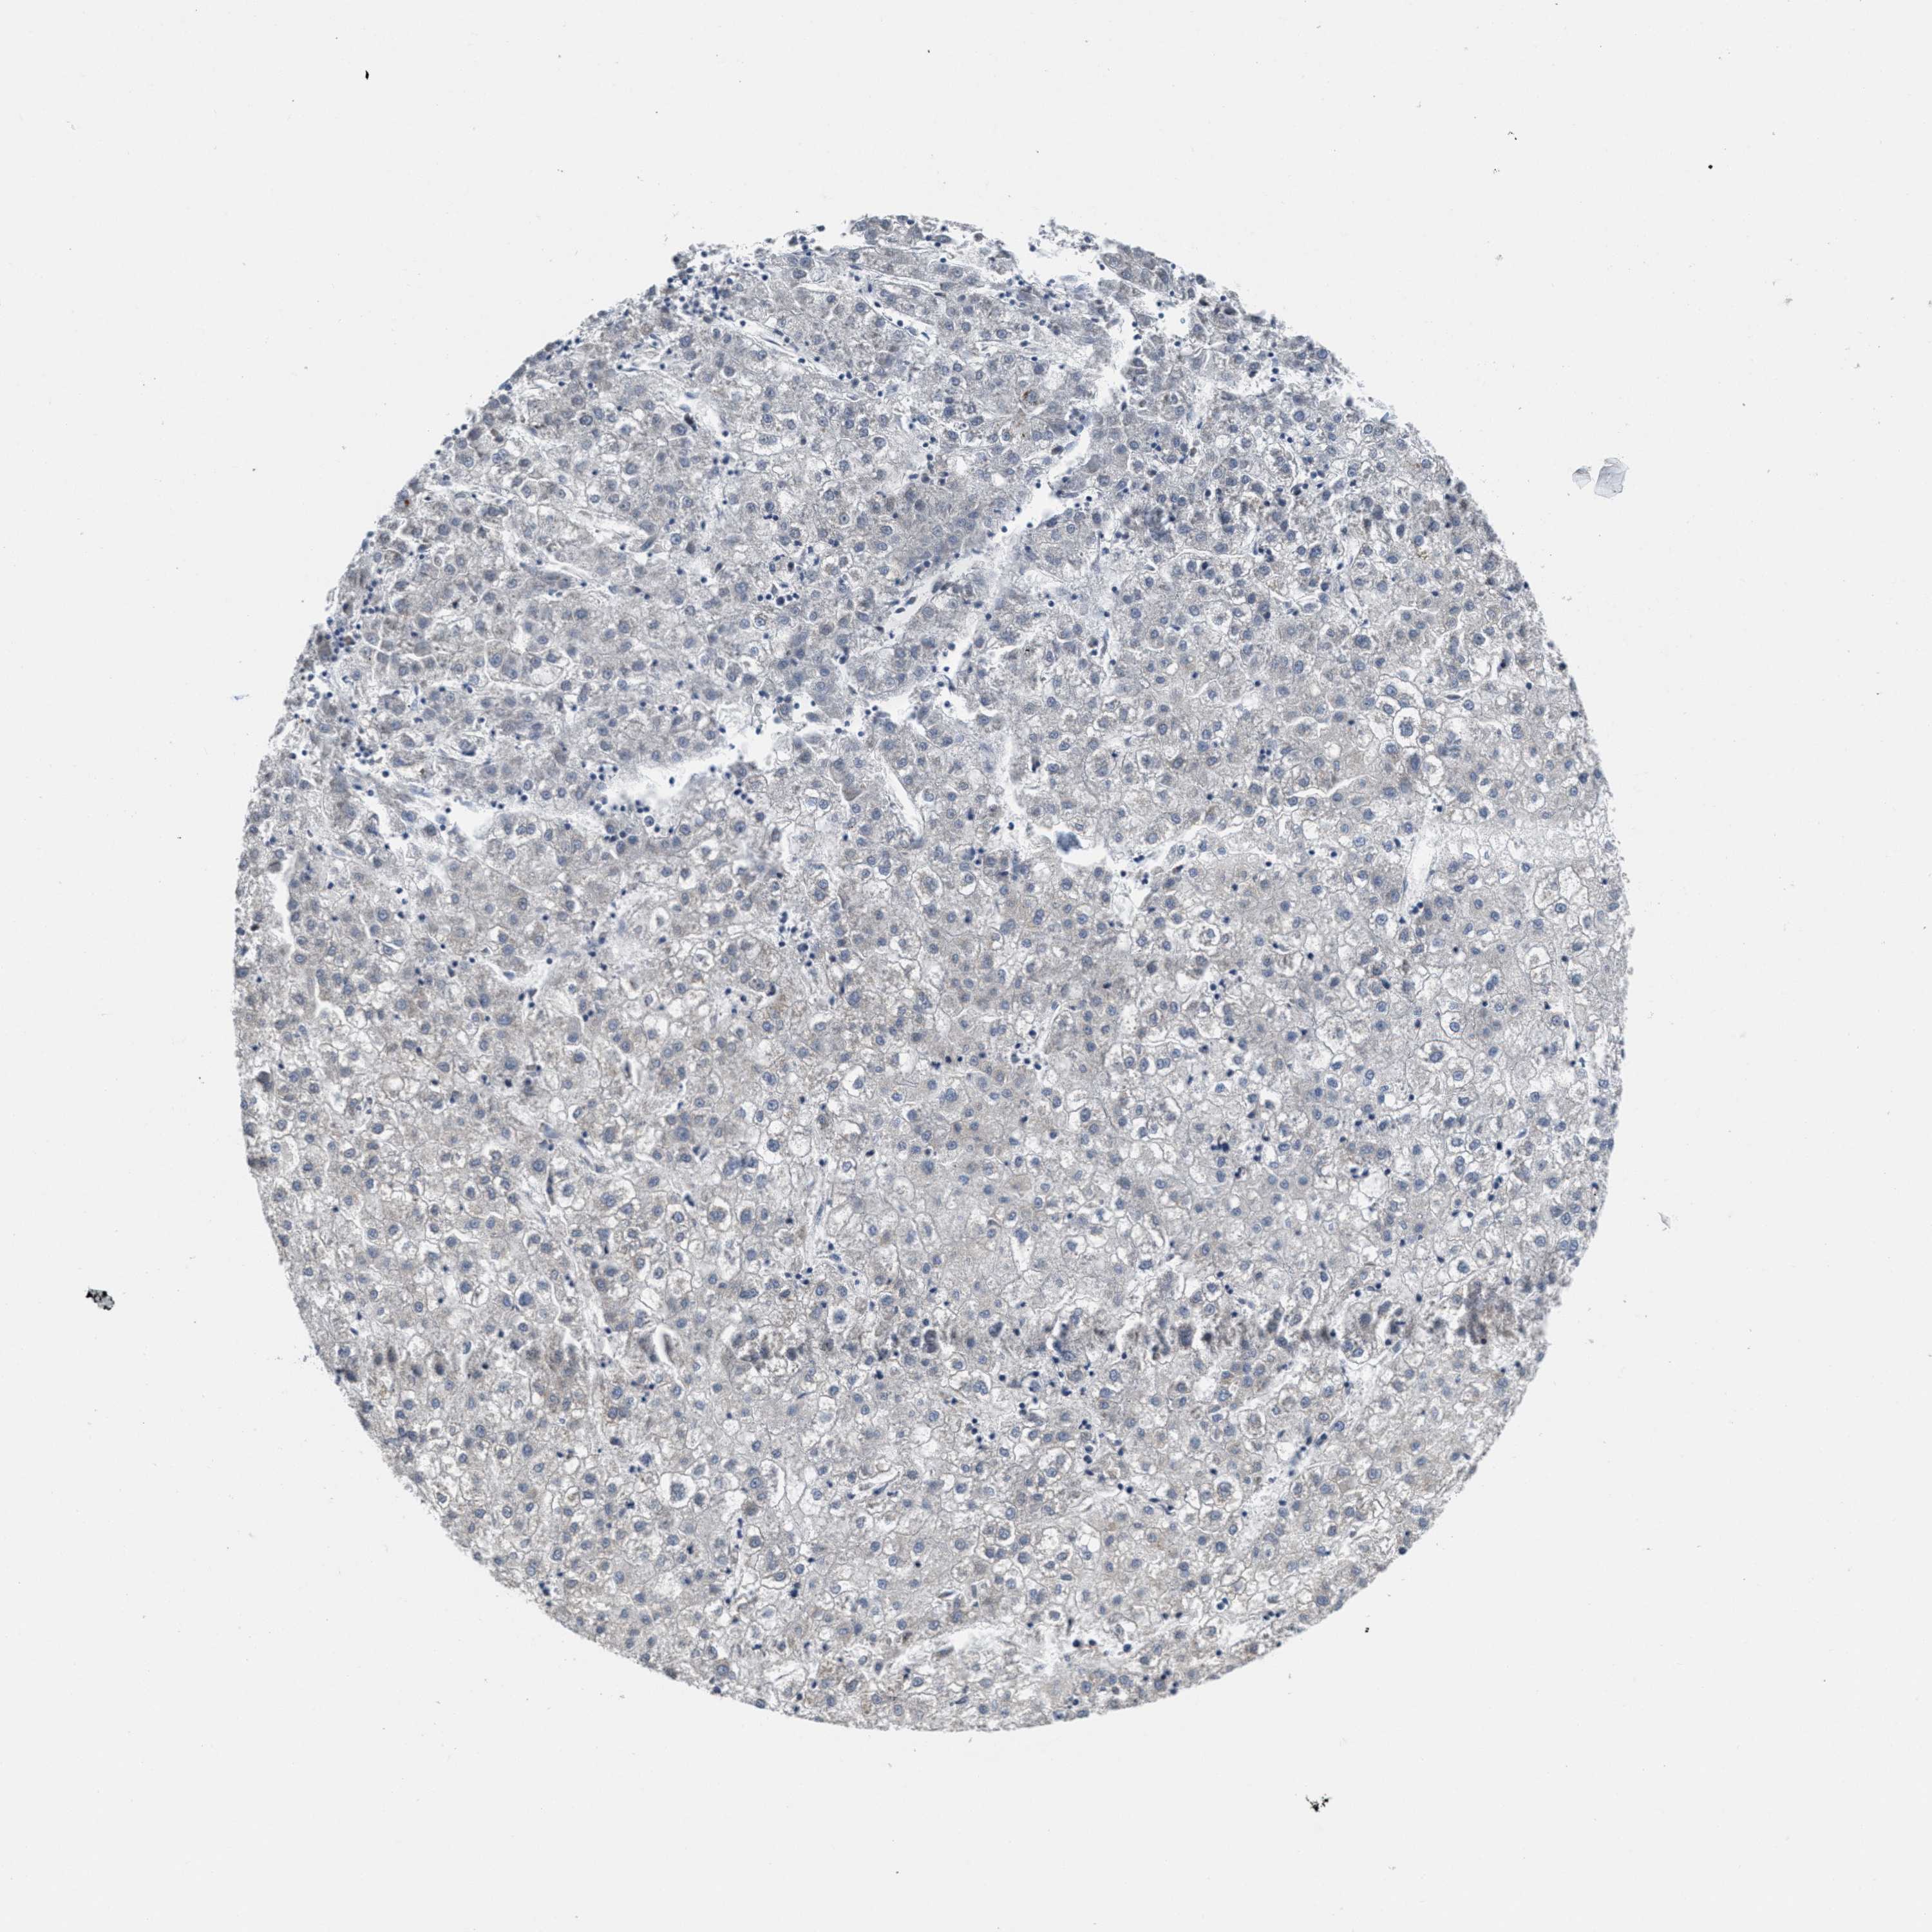

LIVER CANCER - Protein expressioni

A mouse-over function shows sample information and annotation data. Click on an image to view it in a full screen mode. Samples can be filtered based on level of antibody staining by selecting one or several of the following categories: high, medium, low and not detected. The assay and annotation is described here.

Note that samples used for immunohistochemistry by the Human Protein Atlas do not correspond to samples in the TCGA dataset.

Antibody stainingi

Antibody staining in the annotated cell types in the current human tissue is reported as not detected, low, medium, or high, based on conventional immunohistochemistry profiling in selected tissues. This score is based on the combination of the staining intensity and fraction of stained cells.

Each image is clickable and will lead to virtual microscopy that enables deeper exploration of all samples and also displays staining intensity scores, fraction scores and subcellular localization as well as patient and tissue information for each sample.

Antibody HPA018793

Antibody HPA018816

Antibody CAB017815

Staining

High

Medium

Low

Not detected

Intensity

Strong

Moderate

Weak

Negative

Quantity

>75%

75%-25%

<25%

None

Location

Nuclear

Cytoplasmic/membranous

Cytoplasmic/membranous,nuclear

Carcinoma, Hepatocellular, NOS

Cholangiocarcinoma